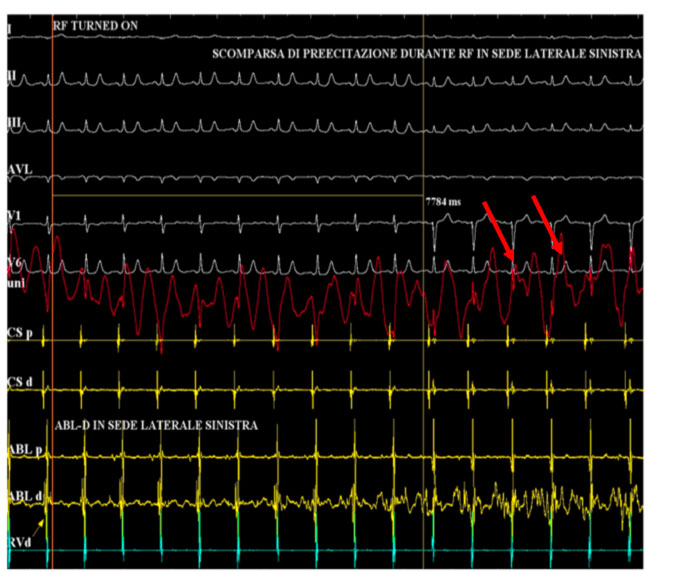

In tale sede si eroga radiofrequenza con scomparsa della preeccitazione ventricolare

Si noti come il segnale atriale e ventricolare appaiano più distanziati sul dipolo in seno coronarico.